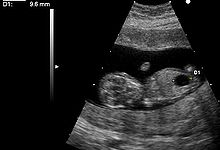

Ultrasound

Ultrasound imaging can be used to screen for Down syndrome. Increased fetal nuchal translucency (NT) is an indicator of increased risk of Down syndrome. A 2003 systematic review of 30 studies of NT in Down syndrome found an average sensitivity of 75-80% with a false positive rate of 5.8-6% (95% confidence intervals). Therefore, while the false positive rate is too high for NT to be used alone as a screening test, it is useful as part of a combined test. Ultrasound measurement of NT is usually performed between 11 and 14 weeks gestation.

Other ultrasound findings have been associated with Down syndrome. Absence of the fetal nasal bone has been associated with Down syndrome. A 2001 observational study suggested that there is an increased rate of absence of nasal bone in fetuses with Down syndrome. However, it is unclear how useful this would be as a screening test as the reproducibility and consistency of the procedure has not been demonstrated.